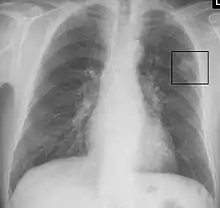

Radiographie de face du thorax montrant un probable cancer du poumon (taches claires sur le côté externe de chaque poumon).

Radiographie de la poitrine montrant une tumeur cancéreuse dans le poumon gauche sous forme d'une opacité ovale.

La radiographie thoracique est la première mesure à prendre si un patient se plaint de symptômes pouvant suggérer un cancer du poumon. Ceci peut révéler une masse évidente, un élargissement du médiastin (qui suggère une extension aux ganglions lymphatiques qui s'y trouvent), une atélectasie (affaissement), une inflammation (pneumonie) ou un épanchement pleural. En l'absence de signes radiographiques, mais si les soupçons sont élevés (par exemple, un gros fumeur avec hémoptysie), une bronchoscopie ou un scanner peuvent donner l'information nécessaire. La bronchoscopie ou la biopsie guidée par scanner sont souvent utilisées pour identifier le type de tumeur[3].